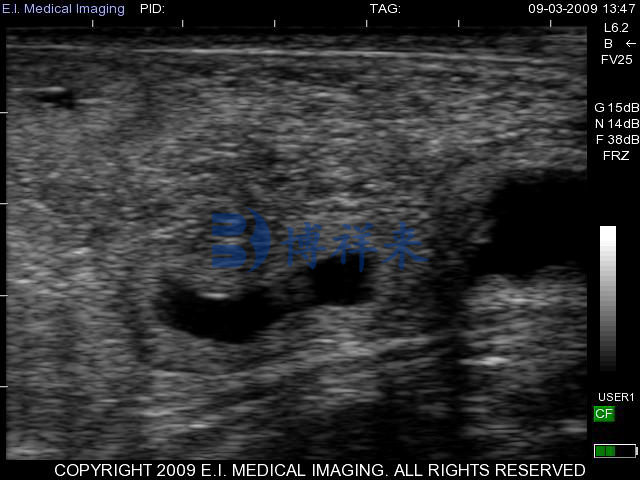

在配种后约 21 天 左右,使用高频 B 模超声在直肠位置扫描 子宫角部,最早可见到充满液体的孕囊(无回声暗区)。此时孕囊较小,边缘呈亮白色子宫壁包围,是确认怀孕的首要图像标志。

配种 21–25 天:孕囊出现但大小不一,只有液性暗区,需耐心扫查子宫角。

约 25–30 天:可见胚体雏形以及逐渐增强的回声,部分病例可通过 M 模观察到弱的规律性心跳信号,这意味着胚胎存活。学术研究指出,在此阶段胚胎及心跳在 19–24 天之间就可能被检测到。